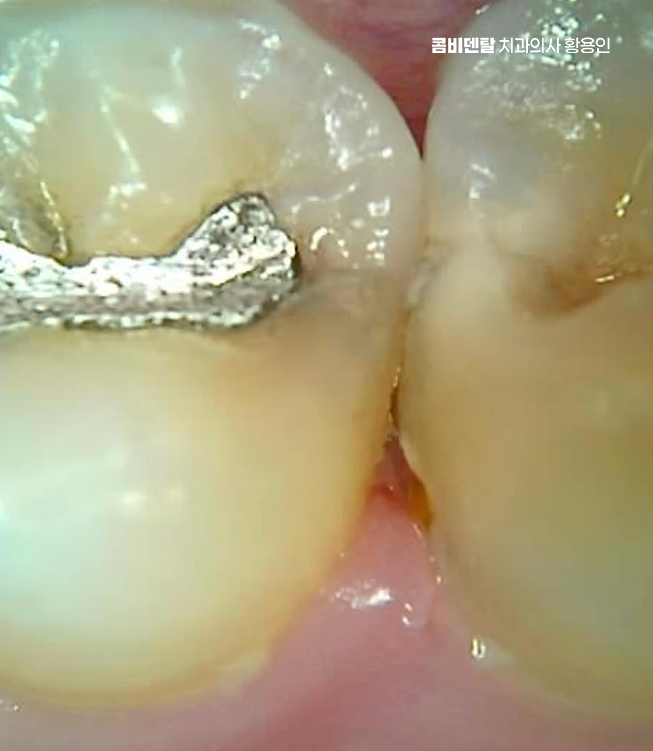

처음엔 안 보일 정도의 크랙이 생기고, 그 사이로 음식물과 세균이 침투하면서 2차 충치가 생기기 쉬운 것이며 특히 어금니처럼 씹는 힘이 센 부위에 들어간 아말감은 이런 팽창으로 인해 치아에 미세한 금을 만들고, 결국은 깨지거나 뿌리까지 손상이 가는 일이 생길 수 있기 때문에 늦지 않게 아말감 교체 레진 같은 재료로 재치료를 고려해야 할 수 있었어요

다음으로 아말감은 경계 부식이 문제가 될 수 있는데 접착력이 비교적 약한 편이라 시간이 지나면 테두리가 들뜨거나, 잇몸과의 접촉면에 틈이 생길 수 있고 이 틈은 결국 충치가 다시 생길 수 있는 통로가 될 수 있으며 아말감 아래쪽에 숨어서 진행되는 충치는 눈에 잘 띄지 않아서 발견이 늦어지는 경우가 많아서 나중에 발견되었을 땐 이미 신경까지 번져 있는 경우도 많이 있었어요